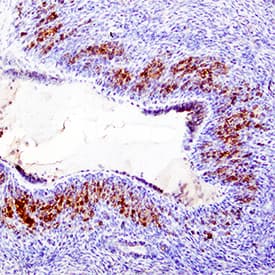

MIF antibody in Human Ovary by Immunohistochemistry (IHC-P).

MIF in Human Ovary.

MIF was detected in immersion fixed paraffin-embedded sections of human ovary using Mouse Anti-Human/ Mouse MIF Monoclonal Antibody (Catalog # MAB2892) at 15 µg/mL overnight at 4 °C. Tissue was stained using the Anti-Mouse HRP-DAB Cell & Tissue Staining Kit (brown; Catalog # CTS002) and counterstained with hematoxylin (blue). Specific staining was localized to epithelial cells. View our protocol for Chromogenic IHC Staining of Paraffin-embedded Tissue Sections.